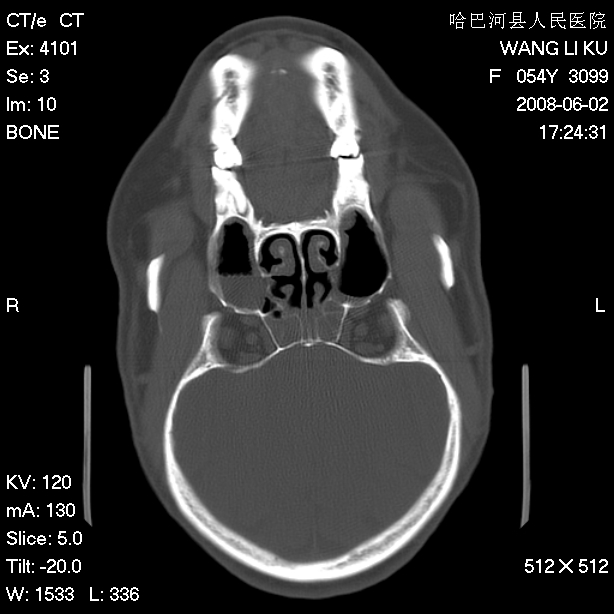

标题: CT13803:反复性鼻塞、流涕一年余 [打印本页]

标题: CT13803:反复性鼻塞、流涕一年余

副鼻窦炎,右上额窦积脓。左眼肌锥内见致密影,视神經受压

1.全组副鼻窦炎2.双侧上颌窦积液

1)全副鼻窦炎(左侧上颌窦黏膜下囊肿或息肉)。2)左眼眶肌锥内不规则小结节状软组织密度影;考虑为小血管瘤可能。建议行ct增强扫描检查。

全组副鼻窦炎,左侧肌锥内不规则形软组织肿块影,与眼外肌密度相当,左侧视神经受压,肿块与视神经及眼外肌分界清晰,眼外肌无增粗,眶壁无破坏,球后脂肪间隙不模糊,考虑良性改变,小血管瘤或神经源性肿瘤可能,建议增强扫描。

谢谢,增强扫描做了,眶内病灶与海绵窦同步明显强化,血管瘤